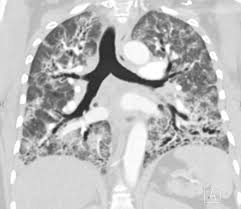

World map of Antisynthetase syndrome. ICD-10-CM Diagnosis Code G463 convert to ICD-9-CM Brain stem stroke syndrome. Antisynthetase syndrome Clinical manifestations Prevalence Myositis 90 Interstitial lung disease 60 Arthritis 50 Raynauds phenomenon 40 Fevr20 Mechanics hands 30 Lung involvement.

Antisynthetase syndrome Disease definition A rare idiopathic inflammatory myopathy IIM characterized principally by myositis generally symmetrical arthritis and interstitial lung disease ILD in association with serum autoantibodies to aminoacyl-transfer RNA synthetases anti-ARS. ICD-10-CM Diagnosis Code S14122D convert to ICD-9-CM Central cord syndrome at C2 level of cervical spinal cord subsequent encounter. Rüegg CA et al.

Antisynthetase syndrome is a set of symptoms that typically occur for patients who have myositis together with one of several specific autoantibodies known as antisynthetase antibodies. 816 Reticuloendothelial and immunity disorders without ccmcc.